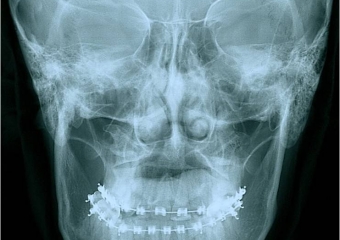

Telerradiografia frontal inicial - Clínica Cliniface

Telerradiografia frontal inicial